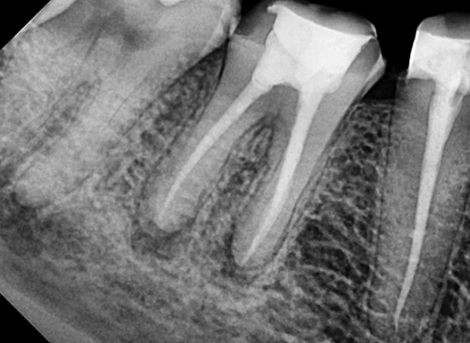

Sealing the Canal

Restoration